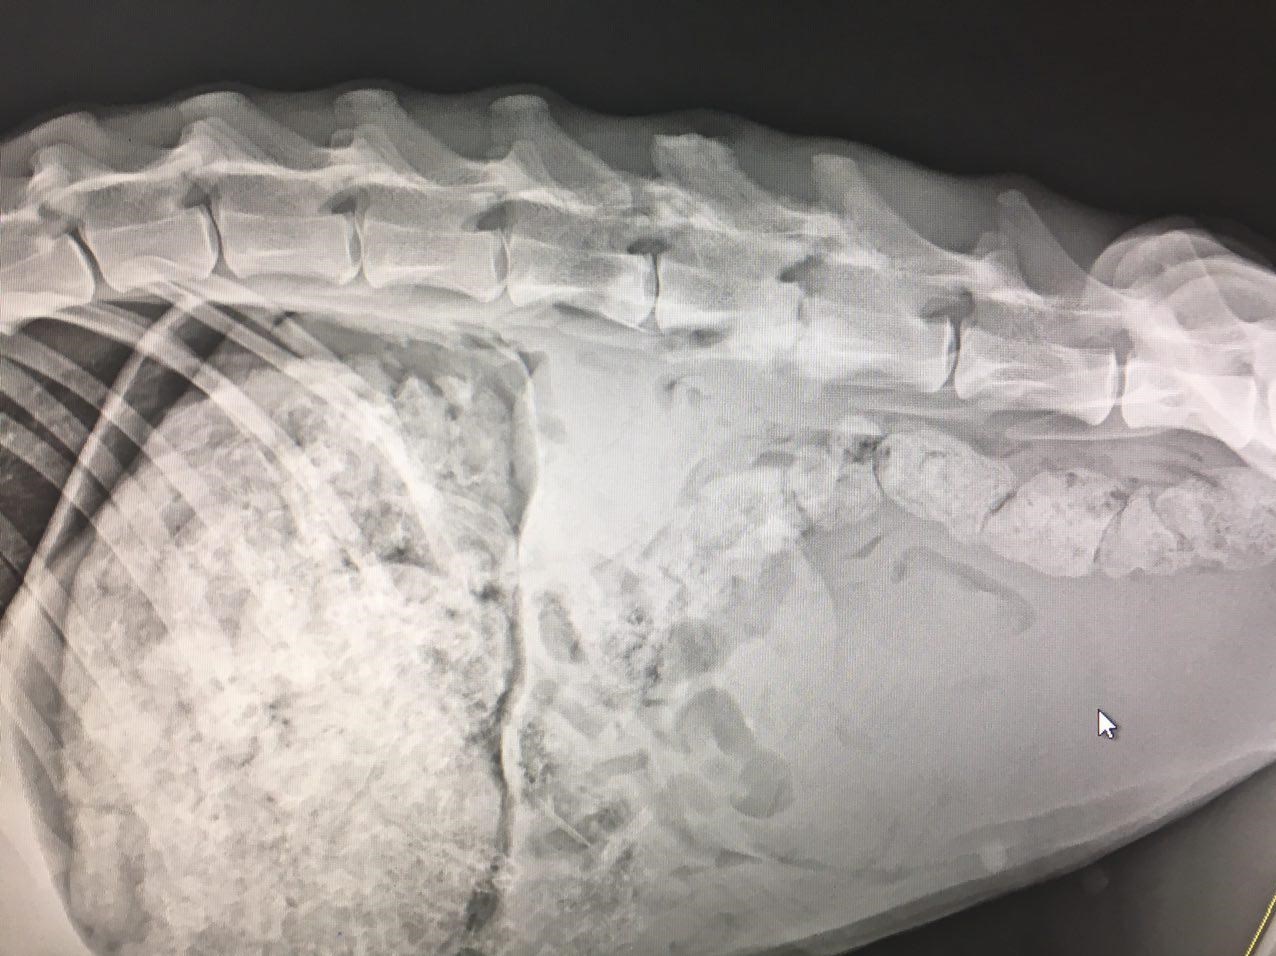

پلنگ انتقالی پس از انجام مرحله بیهوشی، به بخش تصویربرداری ارجاع و سپس تحت پرتونگاری جانبی ستون فقرات، قفسه صدری و نمای پشتی جانبی مهره ها قرار گرفت. پس از آن از بیمار خون گیری شد و جهت بررسی های هماتولوژی و بیوشیمیایی به آزمایشگاه تشخیص طبی بیمارستان ارسال گردید، ضمنا اولترا سونوگرافی شکم جهت بررسی وضعیت اندام های داخلی، بالاخص مثانه، انجام شد. پلنگ مورد نظر، با تشخیص جا به جایی مهره های چهار و پنج کمری، تحت عمل جراحی قرار گرفت. پس از انجام پروسه آماده سازی بیمار و با ملاحظات دقیق و پایش مداوم علایم حیاتی، ضمن ایجاد انسزیون پشتی – جانبی در محاذات مهره های آسیب دیده و جدا نمودن بافت های عضلانی و همبندی در هر طرف، مهره ها اکسپوز گردید. در سطح مفصلی فست ها، بافت همبندی هایپر تروف و وجود کالوس ترمیمی به دلیل اسلایدینگ و جا به جایی در محل، برداشته شد. بررسی دقیق از لامینای مهره ها، شکستگی وتغییرات پاتولوژی بافتی را حداقل در کورتکس خارجی نشان نداد و همچنین در سطح ماکروسکوپی واکنش های عفونت استخوانی در ساختار اطراف مهره مشاهده نگردید. سپس با جداسازی عضلات مجاور دو مهره چهارم و پنجم، جسم مهره مورد بررسی قرار گرفت و تغییرات شکستگی و جا به جایی در جسم مهره ها یافت نشد. سپس موضع مورد نظر با روش دیسترکشن به وسیله دیسترکتور مهره ای، ریداکشن جا به جایی و اسلایدینگ دو مهره نسبت به هم صورت پذیرفت، سپس تحت فلورسکوپی حین عمل به صورت بایلترال جسم مهره های آسیب دیده با پلیت استخوانی DCP و پیج های کورتیکال سلف تپ، استبلایز گردید. پس از تایید قرار گیری مناسب و دقیق پیج ها و پلیت ها و شستشوی سایت عمل با محلول حاوی آنتی بیوتیک وسیع الطیف (سفازولین) عضلات اپکسیال بخیه شد. سپس بافت زیر جلد و جلد با نخ قابل جذب بخیه گردید. پس از اتمام عملیات جراحی، رادیوگرافی بعد از عمل نیز تهیه شد.